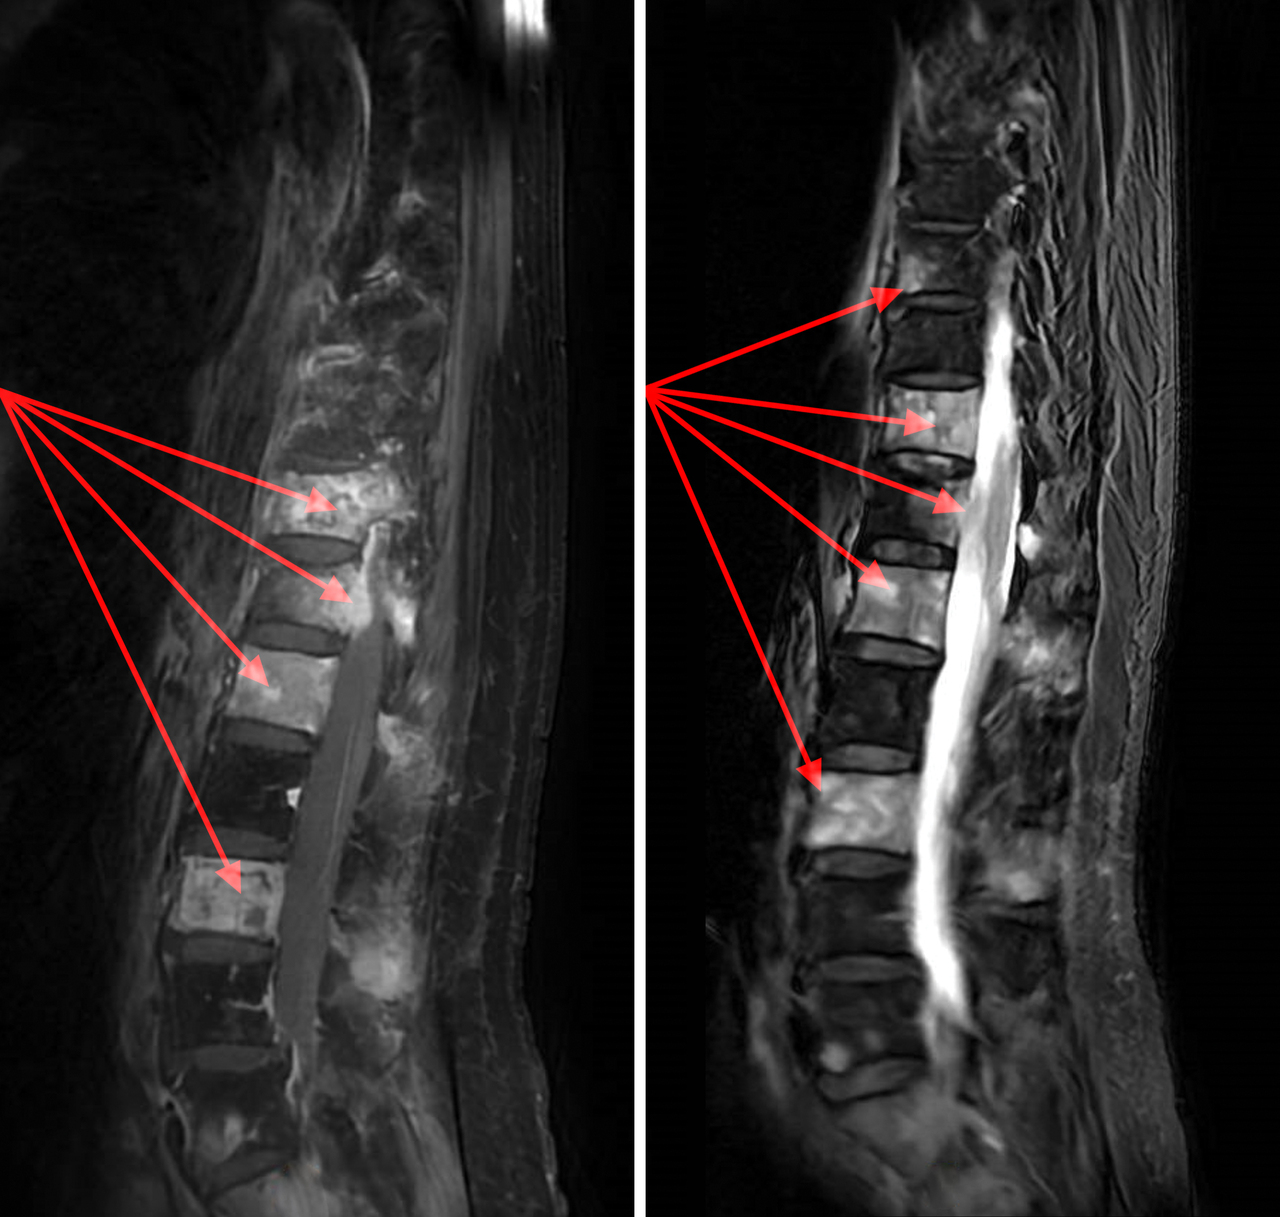

L’IRM rachidienne montre une infiltration médullaire rachidienne lombaire diffuse responsable d’une épidurite antéro-latérale gauche à hauteur de T12, envahissant le foramen homolatéral sans signe de compression médullaire (flèches).